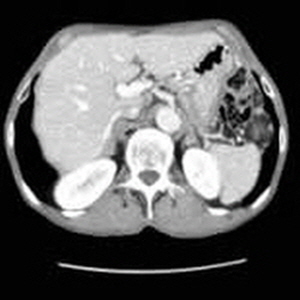

신장은 인체의 대사 노폐물을 제거하고 수분 및 전해질 균형을 유지하는 중요한 역할을 합니다. 신장에 문제가 발생하면 체내의 여러 기능이 부정적인 영향을 받을 수 있습니다. 복부 CT는 신장 결석, 신장 종양 및 기타 신장 관련 질환을 진단하는 데 도움을 줍니다.

신장 결석은 신장에서 형성된 경결된 물질로, 통증을 유발할 수 있습니다. 복부 CT는 결석의 위치와 크기를 정확하게 파악할 수 있으며, 이 정보를 바탕으로 적절한 치료 방법을 결정하는 데 매우 중요합니다. 결석이 발견되면, 물리치료, 약물 치료, 혹은 필요 시 수술이 고려될 수 있습니다. 신장 결석은 수분 보충과 균형 잡힌 식사를 통해 예방할 수 있으므로, 생활 방식의 변화 또한 동반되어야 합니다.